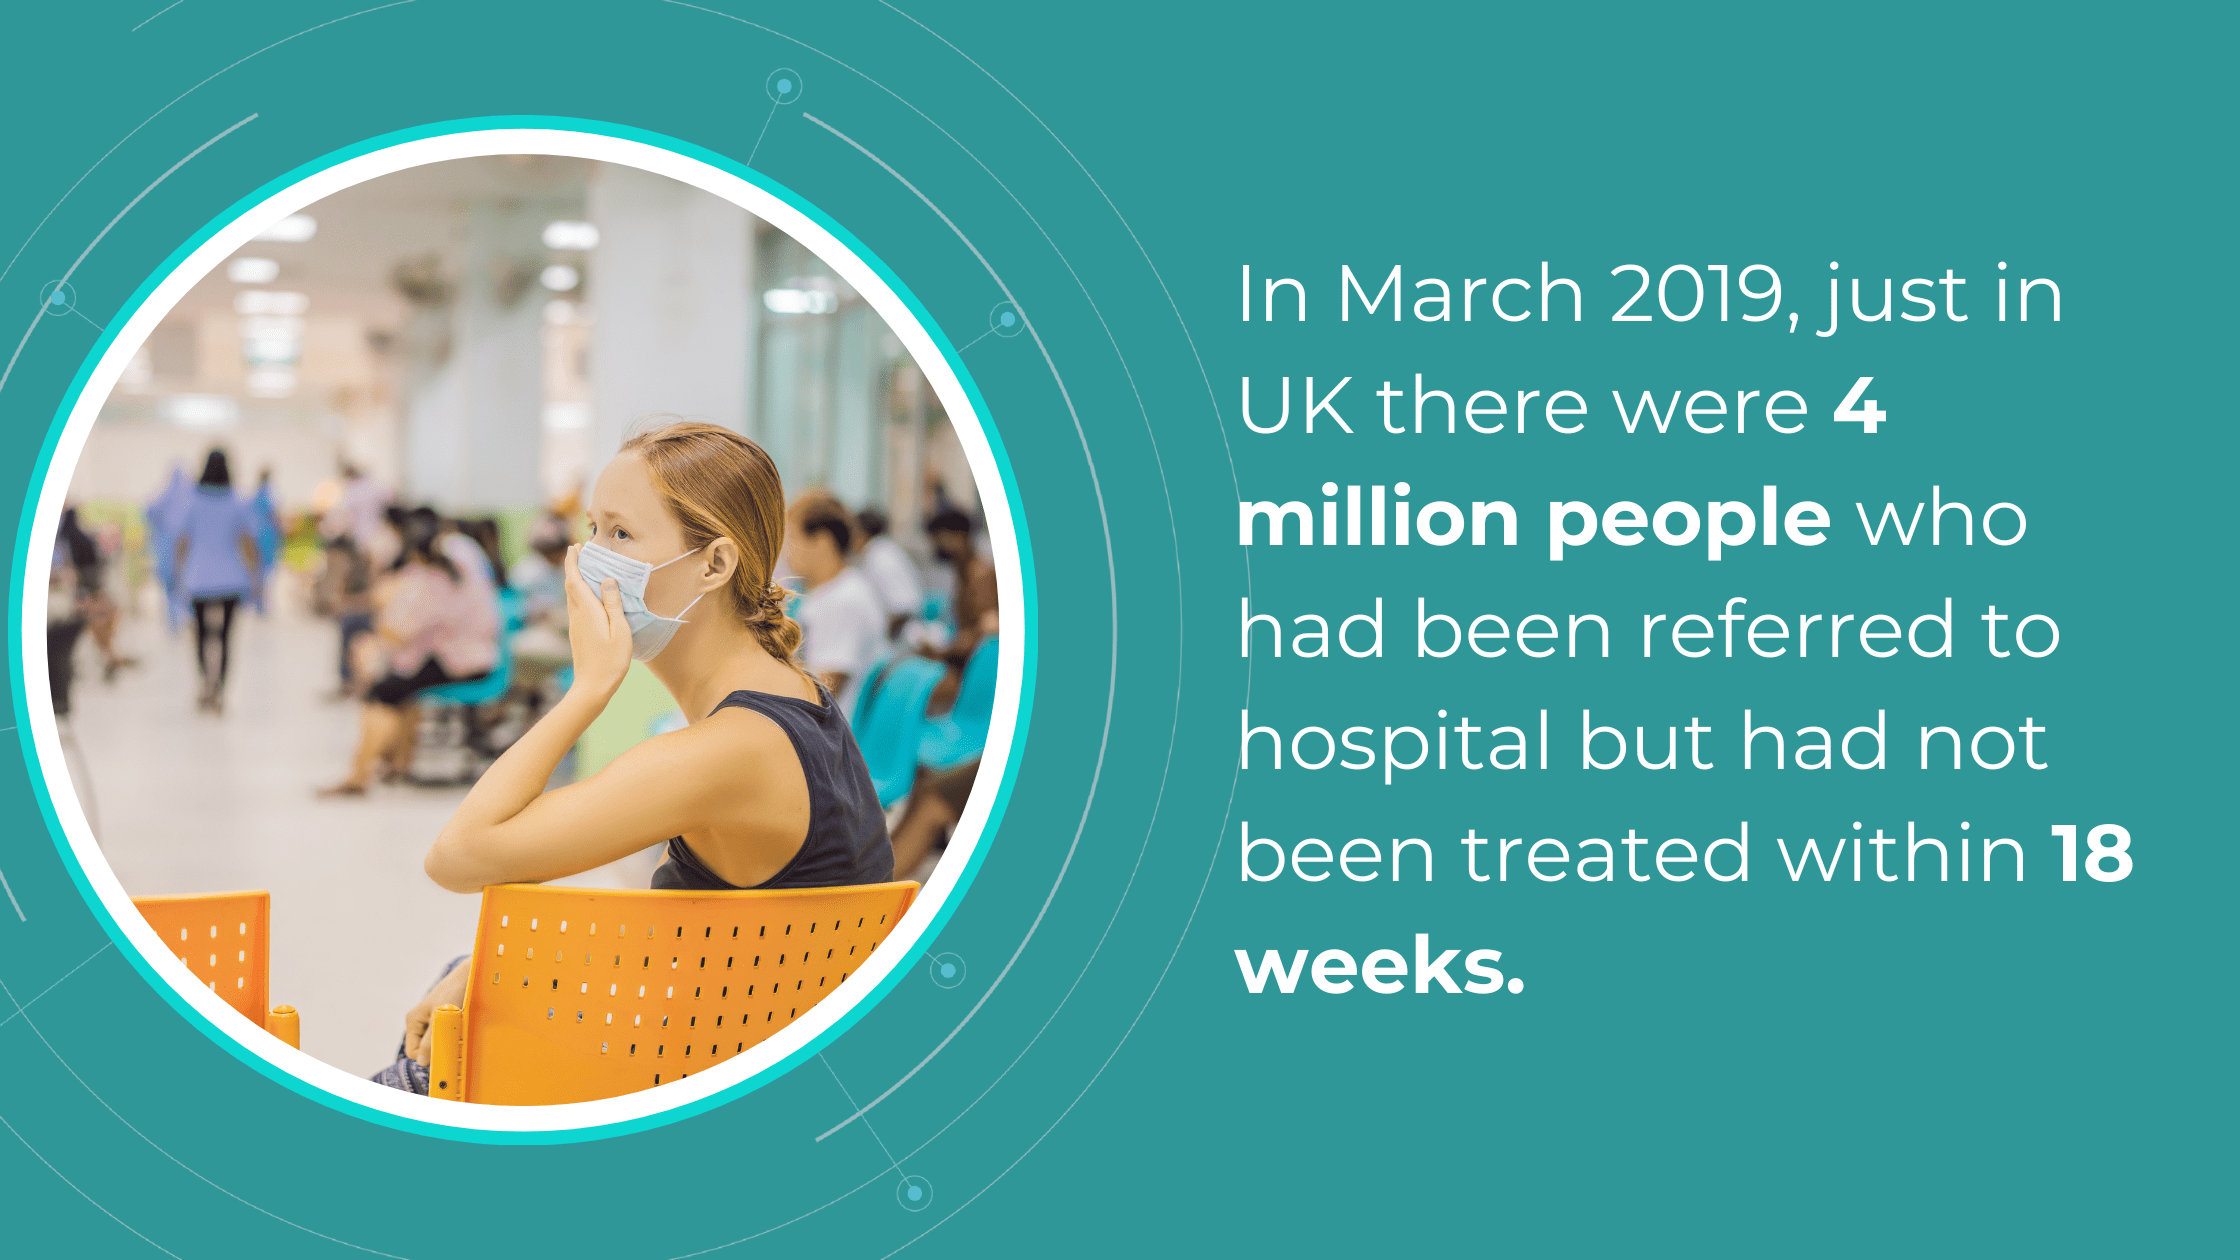

More than 25% of U.S. counties lack a single practicing eye care provider, and the situation isn’t unique to the U.S. In the UK, ophthalmology has been the most overburdened healthcare sector for some time. With a globally aging population and an increasing prevalence of age-related diseases, ensuring accessible eye care is crucial. Unfortunately, the reality is quite the opposite. One contributing factor is the high number of failures in the referral process.

The National Health Service (NHS) is grappling with significant backlogs in ophthalmology services, which account for nearly 10% of the 7.8 million patients awaiting treatment.

The consistently high average number of patients waiting per trust in Ophthalmology, with high follow-up waitlists, delays care that poses substantial risks. The Royal College of Ophthalmologists reported that the risk of permanent visual loss is nine times higher in follow-up patients than in new patients. With 30% more patients on ophthalmology waitlists than pre-pandemic, the number of people at risk of sight loss may have increased.